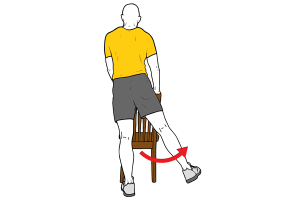

Para ello siempre que se presente una persona con dolor a nivel de la rodilla, vamos a tener que poner también los ojos a nivel de la cadera y a nivel del complejo tobillo-pie. Podemos encontrar disfunciones a nivel de la cadera, que no presenten una sintomatología en la zona afectada y se se manifieste el dolor a nivel de la cadera. Por poner un ejemplo, una disfunción a nivel del glúteo medio en la cara lateral de la cadera, no va a originar un dolor en esa región del cuerpo, sino que con mucha probabilidad va a a desarrollar una molestia en la zona lateral de la rodilla. Todo tiene una explicación: el glúteo medio es un músculo estabilizador del miembro inferior en la fase de apoyo monopodal de la marcha o de la carrera. Si este músculo sufre una disfunción, lo más probable que la cadera supla esta función. Pero a nivel de la rodilla, no vamos a tener una estructura capaz de suplir la función del glúteo medio y su función estabilizadora y por lo tanto la rodilla va a soportar unas cargas demasiado exigentes para la articulación y vamos a empezar a sufrir dolor a ese nivel.

De igual manera pasa con el complejo tobillo-pie. Una disminución en la fuerza del tibial posterior en el apoyo del pie en el suelo, puede desencadenar una modificación de la biomecánica en el momento de la flexión-extensión de la rodilla en el ciclo de la marcha. Muchas veces encontramos adaptaciones o modificaciones en el cuerpo humano que van a suplir estas disfunciones y por norma general no van a suponer problema alguno. Pero si el cuerpo está con una disminución de la fuerza y un estado de alarma muy alto, puede que el dolor se agudice y nos llegue a generar una situación desagradable.